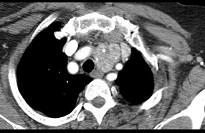

问题 40岁,女,发现颈部肿块,随吞咽上下移动,触之无搏动,咳嗽、气喘1周,请结合CT,检查选择最可能的诊断 ( )

选项 A.胸腺瘤 B.胸内甲状腺瘤 C.无名动脉瘤 D.无名动脉伸展扭曲 E.淋巴瘤

答案 B